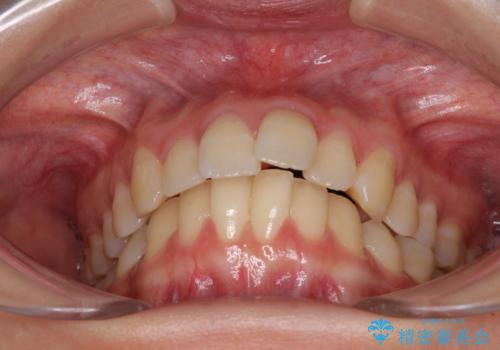

- 前歯の突出感を気にして来院された患者様です。

左右ともに奥歯の咬み合わせが上顎前突となっており、上顎前歯が飛び出している状態でした。

奥歯の咬み合わせはしっかりと改善され、前歯の突出感も改善されました。